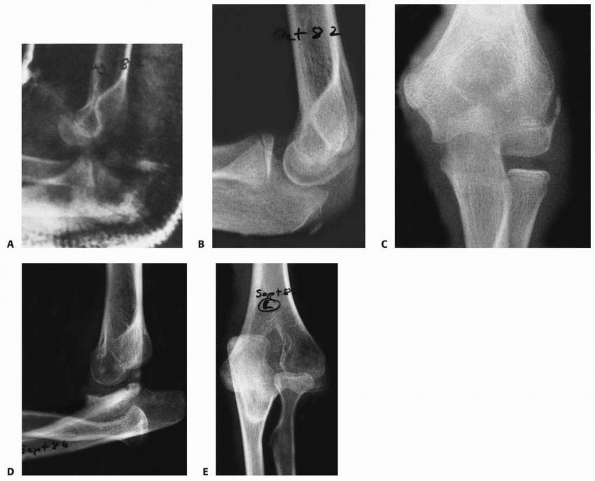

![]() |

FIGURE 16-11 Closed reduction. A. Anteroposterior radiograph of a 9-year-old girl with a posterior dislocation of the right elbow. B. Lateral radiograph shows the proximal radius and ulna posterior to the distal humerus. C. There is a concentric reduction following closed reduction using a puller technique. D. Lateral radiograph.

|

dramatic loss of elbow function characterized by loss of motion and

eventually pain (Fig. 16-7). In comparison,

reduction of the dislocated elbow usually achieves marked improvement

FIGURE 16-7 Unreduced dislocation. A.

Preoperative anteroposterior radiograph. The elbow sustained an injury 3 years before surgery. Elbow motion was extremely limited and painful. The lateral supracondylar ridge had been eroded by the radial head (arrow). B. Lateral radiograph. The posterior position of the olecranon is apparent. C. Anteroposterior radiograph 3 months postoperatively. Total elbow motion was 30 degrees, but there was less pain and more stability. |